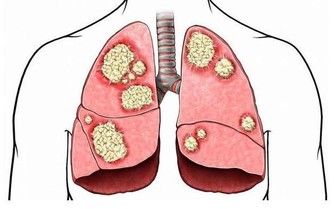

眼睛是心靈的窗戶,感受世界中的美好。當視力出現有障礙的時候,這就令人很頭疼。對於眼科疾病,例如就是青光眼這類的疾病,也是逐漸變得年輕化,因此需要引起我們的重視。

當出現了兩個月眼壓一直降不下來,頭疼難受,也是青光眼的相關症狀。對於繼發性的青光眼,及時治療大部分可以恢復,但可惜的是,青光眼這個危害著人們健康視力的疾病,卻是很容易就被忽視。

目前的研究中也發現,通宵追劇也是有可能成為一個誘發青光眼的因素。青光眼現在發病的人群已經是不分老小,年輕人也是不能夠輕視。當在電影院長時間地看了一場電影之後,有的人也會感覺到眼睛有不適的症狀。又或者是在黑暗的夜里長時間地看手機,甚至是通宵一夜看電視劇,相關報導也有發現這樣子做也會導致出現有青光眼的急性發作。